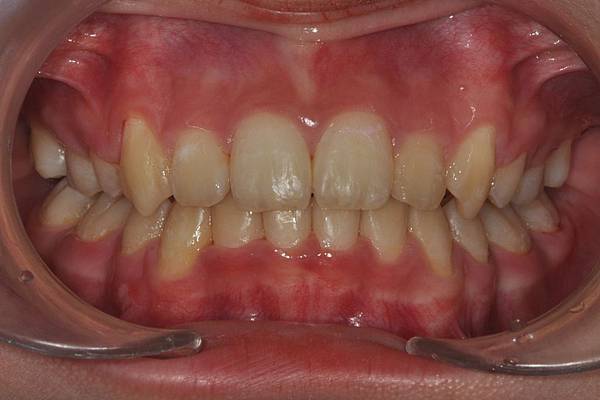

拔牙改善高位虎牙

虎牙妹的女神蛻變之旅~

此案例因為空間不足排列牙齒,

考量到不拔牙將使得牙齒前凸破壞患者原本和諧的側臉。

故上下左右各拔一小臼齒。

治療前/治療後

-以上案例由林昇進醫師提供